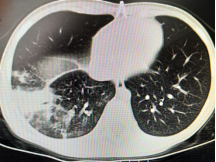

以下为呼吸专业典型病例分享:

图片2:气管狭窄后电切、球囊扩张、二氧化碳冷冻治疗